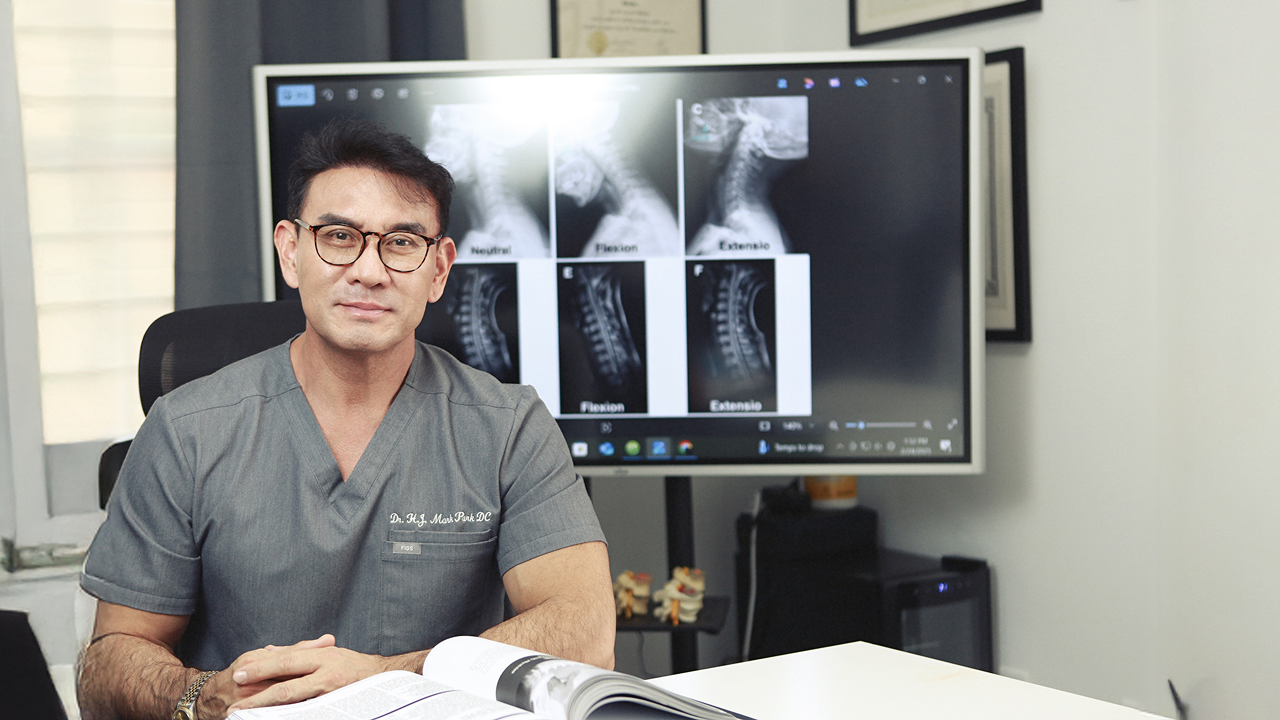

Advanced Injury & DISC Center

Neck Pain Relief

Expert Chiropractic Care in Duluth, GA

Welcome to Advanced Injury & DISC Center, your trusted

chiropractor and neck pain specialist in Duluth, GA. Neck pain can be more than just uncomfortable it can disrupt your daily routine, affect your posture, and decrease your overall quality of life.

Whether your discomfort comes from a workout injury, poor posture, repetitive movements, or a car accident, effective treatment is key to long-term relief.

At Advanced Injury & DISC Center, we understand the toll that neck and shoulder pain can take. That's why we offer comprehensive chiropractic care and advanced therapies to address not just the symptoms, but the root cause.